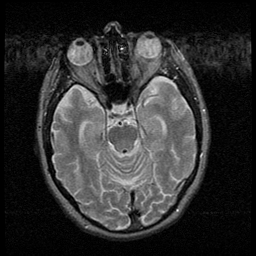

Huntington's Chorea, MR -- Slice #6

[Home][Help][Clinical] Slice 6